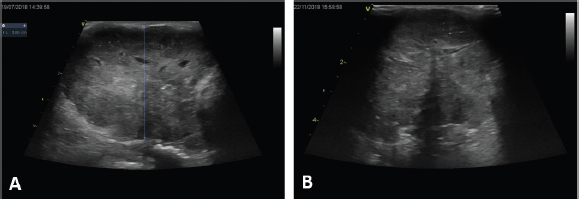

Out of those ten dogs, only one dog received ECT for treatment of microscopic local disease, while in the remaining cases ECT was used to treat the primary macroscopic tumor (Fig. 1A and B) and, if present, the metastatic LNs. In three dogs, ECT was followed by systemic medical treatment including carboplatin, mitoxantrone, and toceranib phosphate.

Fig. 1. Clinical outcome of a large anal sac carcinoma (A) at presentation and (B) after one session of ECT. Note the appearance of a large anechoic formation compatible with necrotic neoplasm.